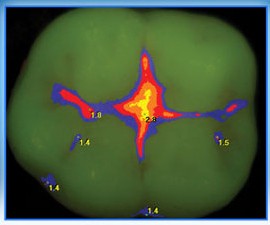

Аномалии строения и пороки развития зубов Пороки тканей зуба многообразны, они могут проявляться изолированно и сочетаться с аномалиями строения и пороками развития органов и систем всего детского организма, в том числе челюстно-лицевой области. Ткани зуба имеют эктодермальное (эмаль) и мезодермальное (дентин, пульпа, цемент) происхождение. В связи с этим пороки эмали […]